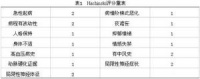

1.老年性痴呆 老年性痴呆和血管性痴呆都是老年人发生痴呆最常见的原因,两者可以单独发生,也可并存

或先后发生。脑血管疾病亦常可使老年性痴呆加重。因此两者存活期的鉴别诊断较困难,最后确诊需病理检查。采用Hachinski缺血量表对老年性痴呆和血管性痴呆进行鉴别在临床上较简单,且具有一定的准确性。即对每一临床特征给1 分或2 分,积7 分以上者符合血管性痴呆,而4分以下者则为血管性痴呆。Hachinski 鉴别积分表:有Hachinski 缺血量表的主要内容,加上了CT 扫描,凡总分低于2 分者可考虑老年性痴呆,3~4 分可拟诊血管性痴呆,4 分以上可确诊血管性痴呆。